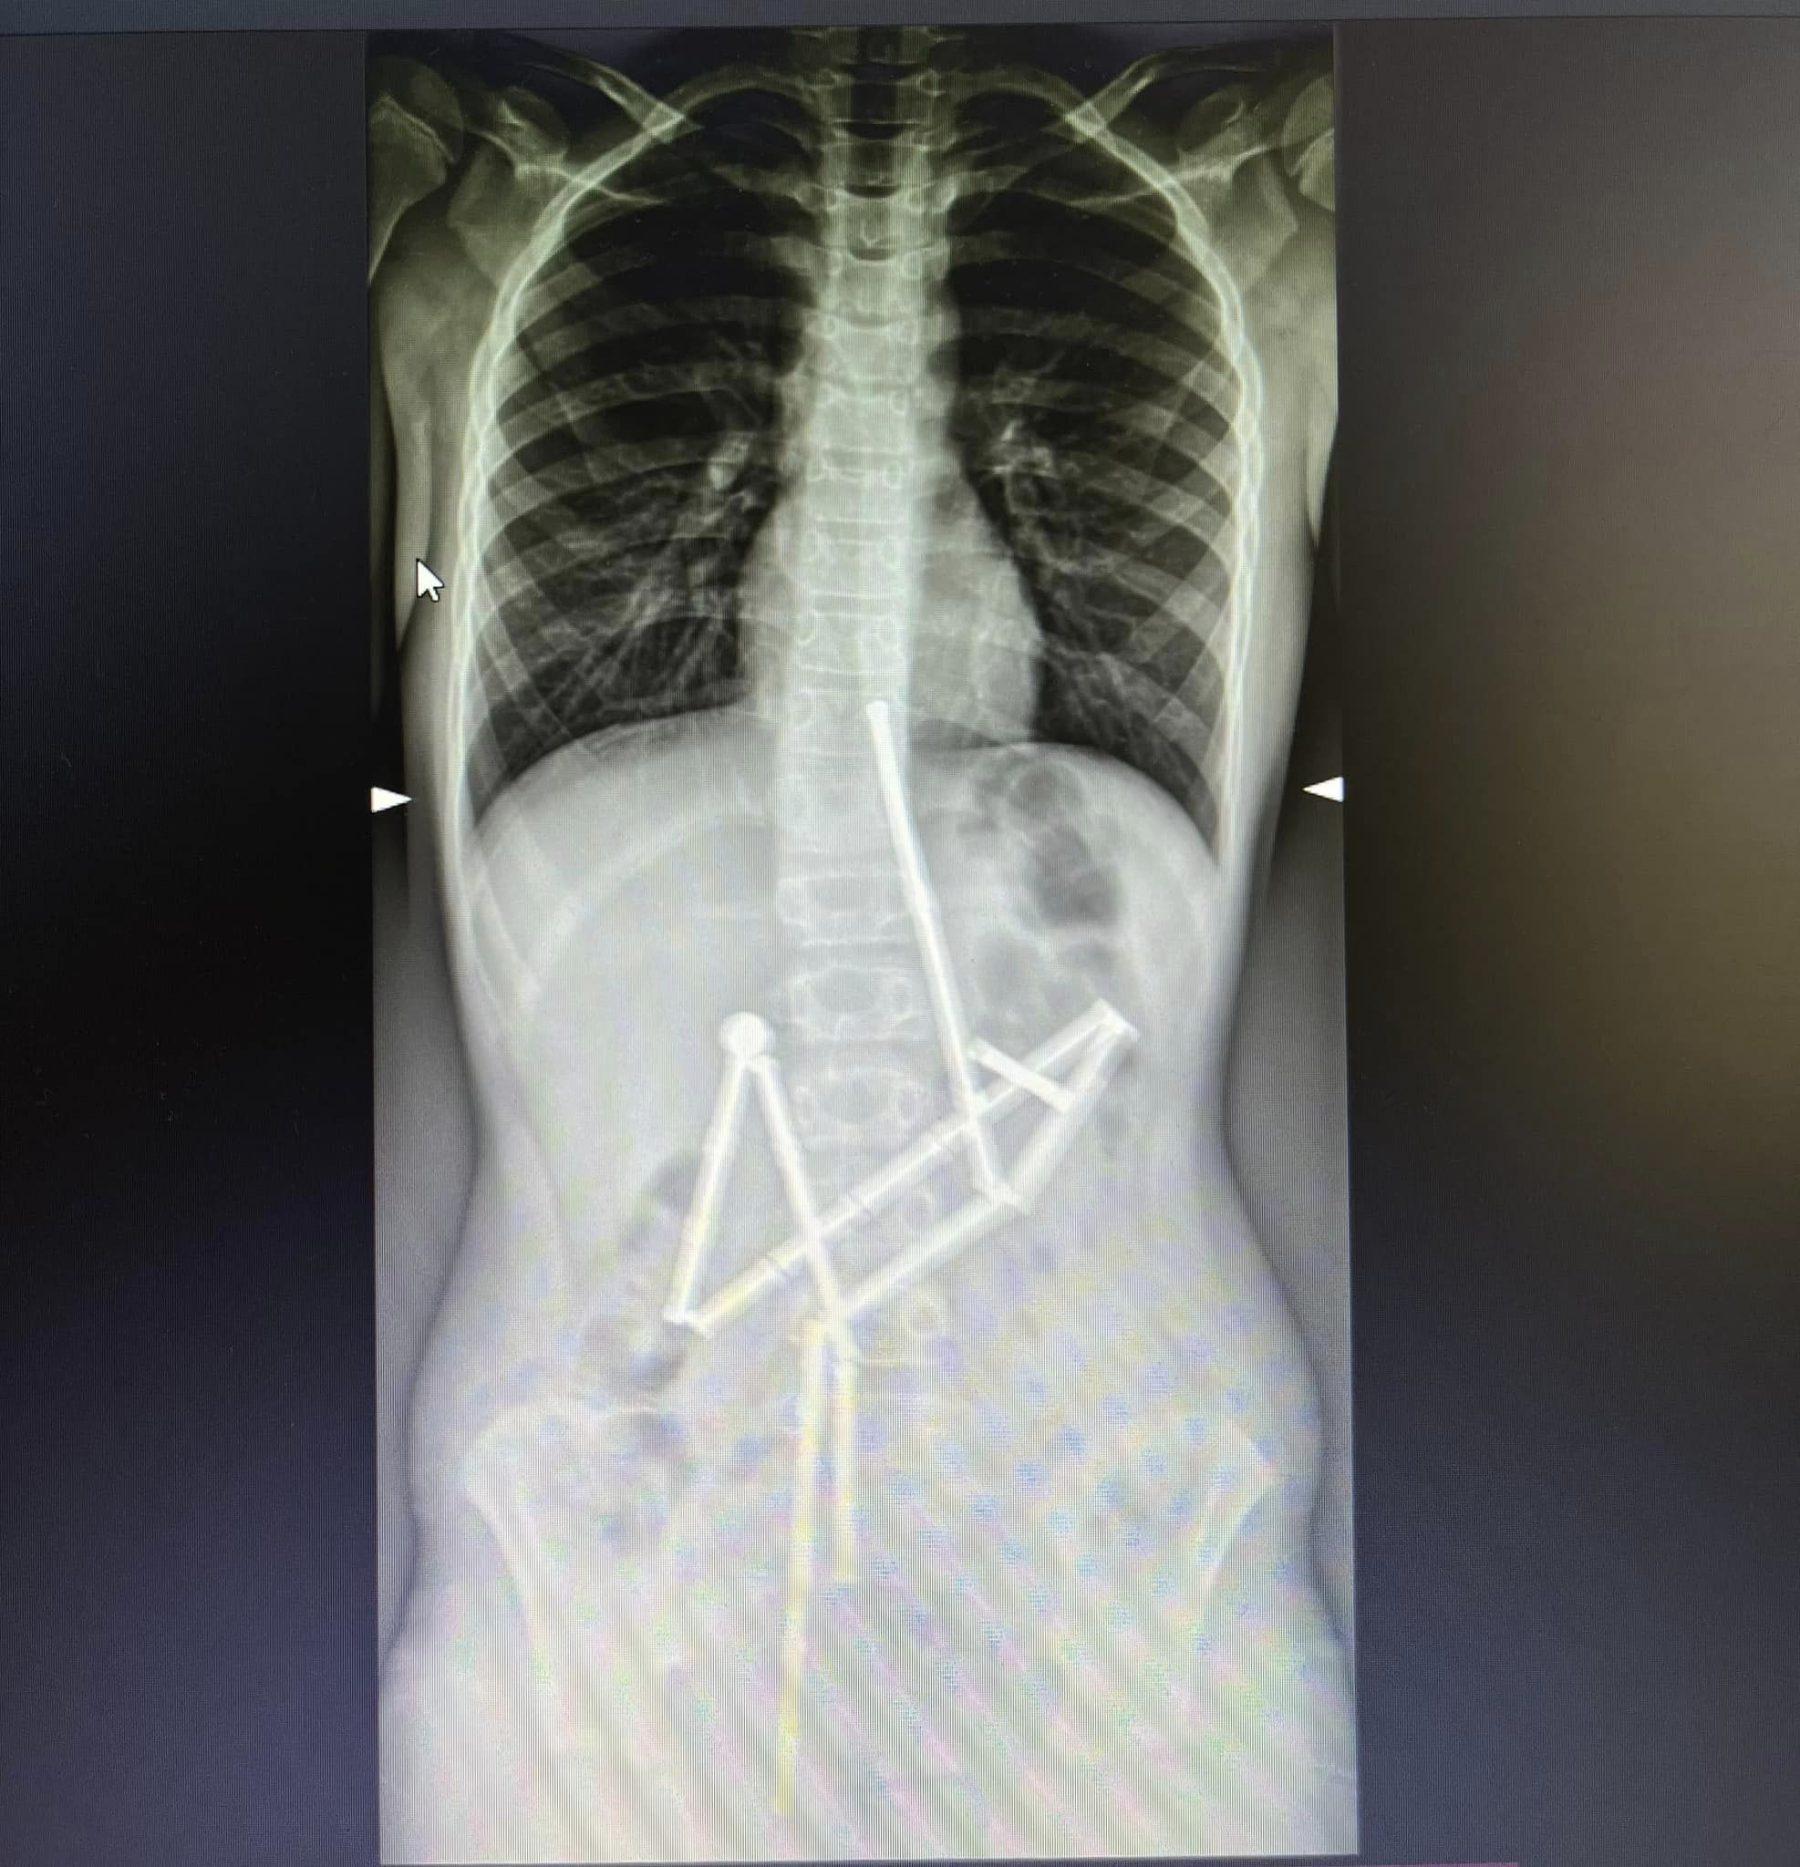

Na rentgenskem posnetku so v otrokovem prebavnem traktu sicer 20 magnetov, ki so bili "zlepljeni skupaj" v dolgo "kačo", poroča UNN. Zdravniki so se odločili za takojšnjo operacijo, saj bi lahko vsaka dodatna ura poslabšala zdravstveno stanje dečka.

Foto: Pediatrična bolnišnica Okhmatdyt | Foto: Pediatrična bolnišnica Okhmatdyt